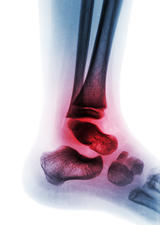

Productivity loss from osteoarthritis will cost Canadian economy $17.5 billion/year by 2031

Rising rates of osteoarthritis (OA) will cost the Canadian economy an estimated $17.5 billion a year in lost productivity by 2031 as the disease forces greater numbers of people to stop working or work less, a study has found. The upsurge in work time loss comes just as Canadian productivity comes up against a momentous challenge: finding enough workers to replace retiring baby boomers after decades of low birth rates.